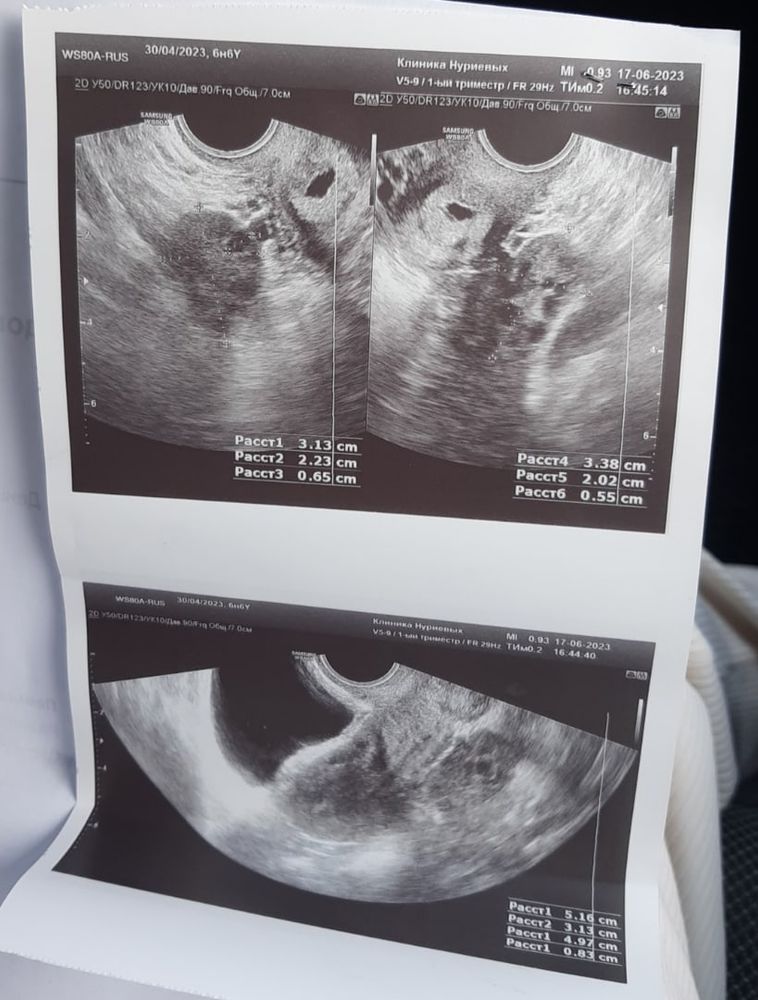

Узи малого таза подростку девочке 118 фото